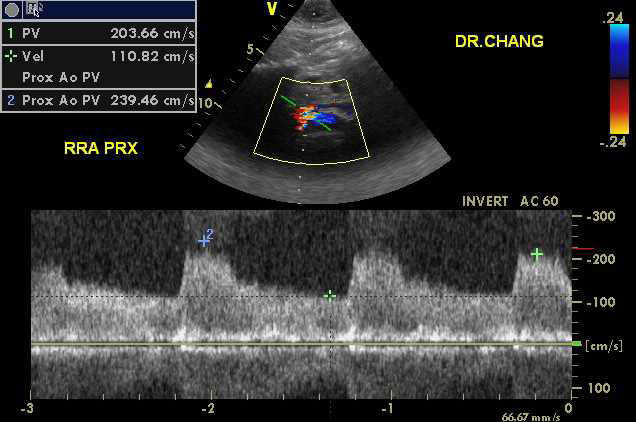

The examination was performed by a registered vascular technologist on a GE Vivid-q ultrasound unit with a M4-S transducer. Gray scale, color and doppler images were obtained from the mid abdominal aorta, the right renal artery and left renal artery. Upon interrogation of the right renal artery, markedly abnormal waveforms and velocities were demonstrated throughout the entire length of the vessel.2 The peak systolic velocity (PSV) was measured at 351cm/sec with an elevated end diastolic velocity of 140cm/sec. The right Renal Aortic Ratio was elevated at 4.3. Of particular interest, color doppler imaging demonstrated a “mosaic” pattern extending from the distal right renal artery into the helium. The left renal artery doppler interrogation was fairly unremarkable with a PSV of 144cm/sec and a Renal Aortic Ratio of 1.78 (Figure 1-3).

Figure 7 Color and Doppler images of RRA FMD.

Figure 8 Color and Doppler images of RRA FMD.

Figure 9 Color and Doppler images of RRA FMD.